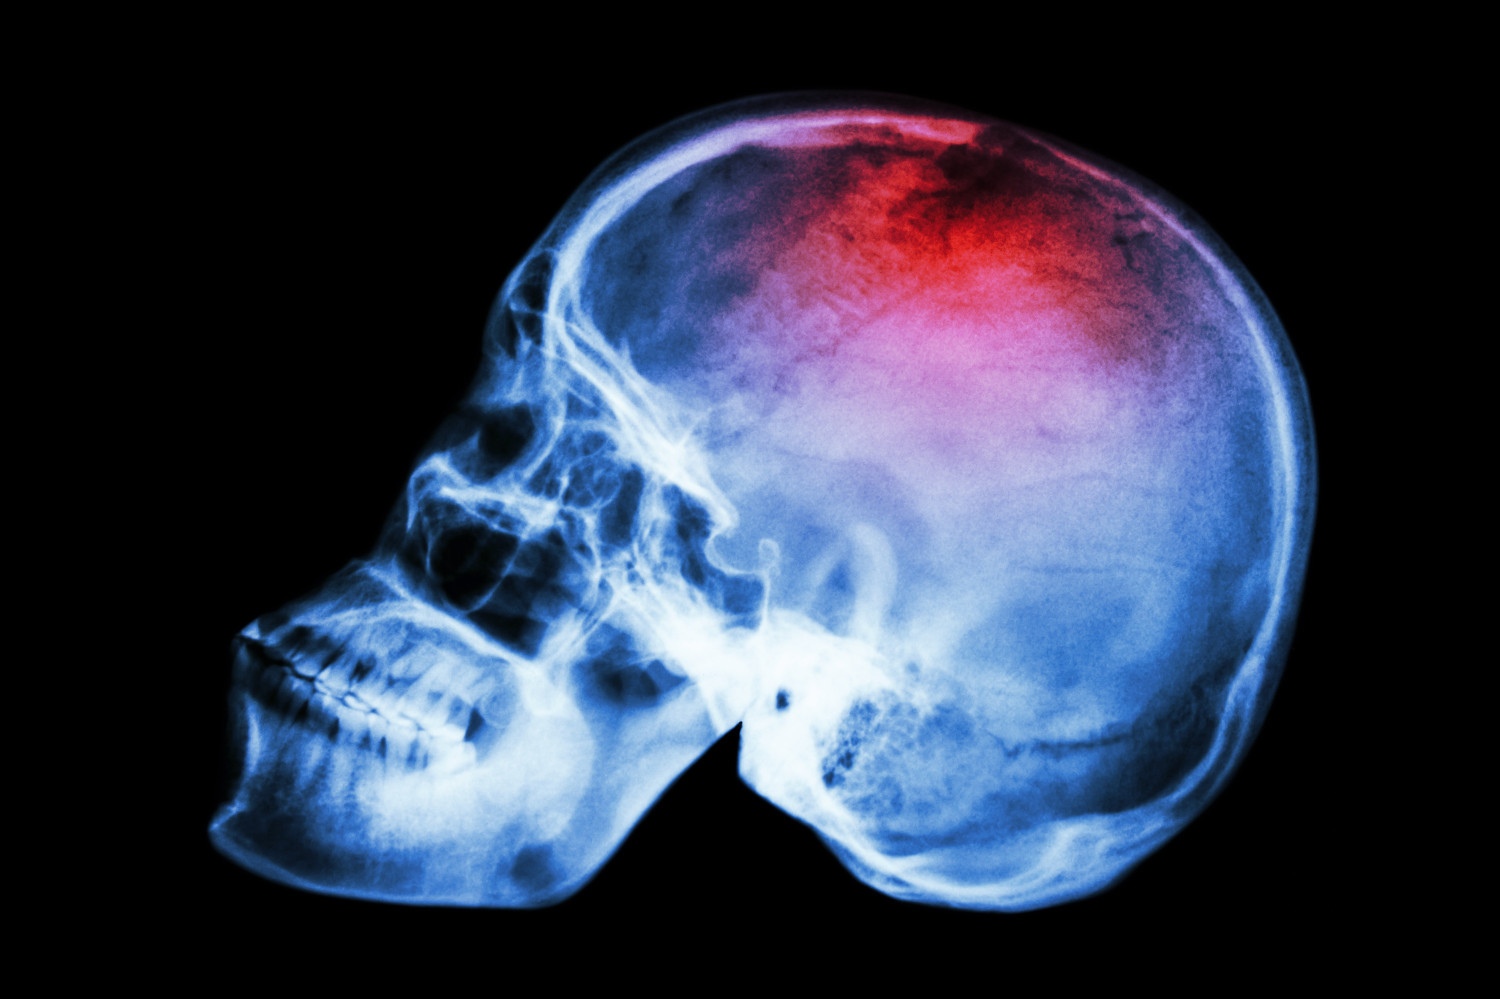

Добавление антикоагулянтов и антиагрегантов не улучшало исходы инсульта

Ученые из Школы медицины Университета Сент-Льюиса оценили эффективность и безопасность добавления антикоагулянтов и антиагрегантов к внутривенному тромболизису у пациентов с острым ишемическим инсультом. Результаты исследования опубликованы в журнале NEJM.

Авторы отмечают, что внутривенный тромболизис – это стандарт лечения острого ишемического инсульта. А эффективность и безопасность добавления антикоагулянтов и антиагрегантов окончательно не изучены.

| Ученые изучили данные 514 пациентов с ишемическим инсультом, которые получили внутривенный тромболизис в течение трех часов после появления симптомов. В течение 75 минут после завершения тромболизиса участникам назначали парентеральный антикоагулянт argatroban (59 человек), антиагрегант эптифибатид (227 участников) или плацебо. |

Спустя 90 дней после начала терапии показатель по модифицированной шкале Ранкина составил 5,2 в группе argatroban, 6,3 в группе эптифибатида и 6,8 в группе плацебо. Эксперты пришли к выводу, что добавление препаратов не снижает частоту инвалидизации после инсульта.

Частота возникновения симптоматических внутричерепных кровоизлияний оказалась сопоставима в трех группах (4% на фоне argatroban, 3% при назначении эптифибатида и 2% при использовании плацебо). Частота летального исхода оказалась существенно выше в группах argatroban (24%) и эптифибатида (12%), чем при введении плацебо (8%).